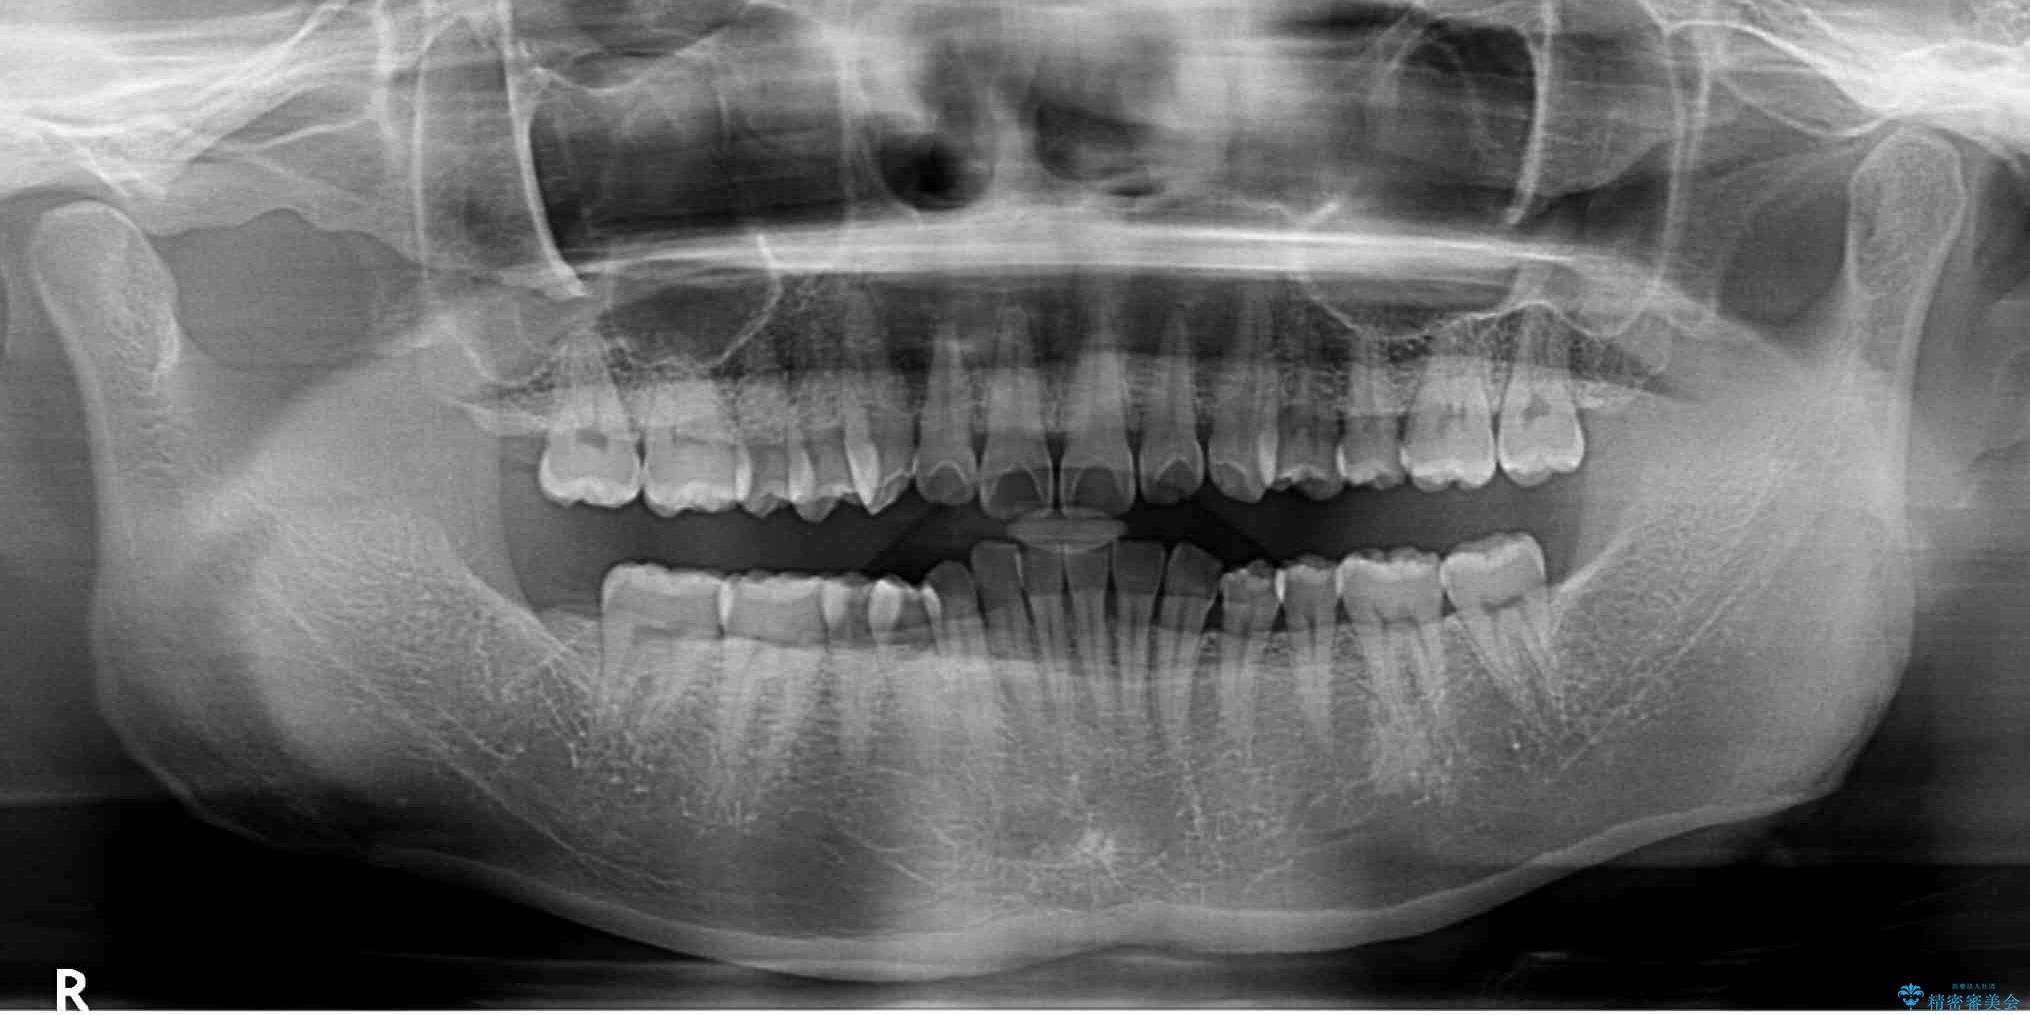

下顎の臼歯が手前に傾斜していることで咬み合わせが深くなってしまい、下顎前歯が見えないほどに上顎前歯が覆い被さっている状態でした。

下顎臼歯を起き上がらせるためにユーティリティーアーチを使用し、一気に深い咬み合わせを改善することができました。